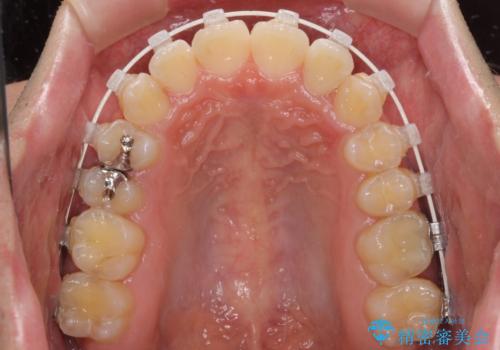

- 上下前歯のデコボコを気にして来院された患者様です。

ワイヤー矯正でもマウスピース矯正でも可能でしたが、短期間で、自身の手を煩わせることなく治療を行いたいとのことで、ワイヤー装置にて矯正治療を行うこととしました。

当初予定通り、1年間で治療を終えることができました。